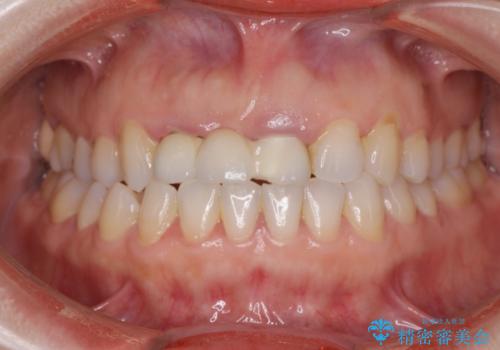

根管治療を行ったのち、歯周外科を行うことで、欠損部の歯ぐきの厚みを出し、縁上歯質を獲得することで、長期的な予後の見込めるブリッジを製作できる環境を整備していきます。

歯周外科をおこなったことで歯ぐきのラインを整え、脱離しないような前歯のブリッジを作製することができました。